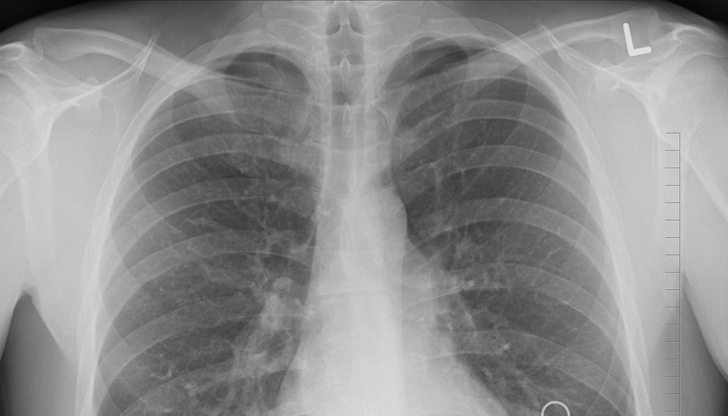

Археологическите находки потвърждават, че туберкулозата заразява хора още от 4000 година пр.н.е. Mycobacterium tuberculosis - причинителят на заболяването, разпознат от Роберт Кох през 1882 година, има неповторимата дарба да остава в спящо положение десетилетия наред. Когато се задейства, нападна белите дробове, а от време на време и други органи.